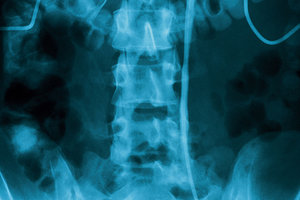

As a general guideline, patients with the following conditions are appropriate candidates for flexion-oriented exercises:

- Lumbar degenerative disc disease / spondylosis

- Spinal stenosis

- Spondylolisthesis

- Sciatica (secondary to spondylosis, stenosis or spondylolisthesis)

- Disc syndromes (Note: MDT extension protocols are also well-referenced in the literature for lumbar disc treatment)

- Facet imbrication (secondary to hyperlordosis)